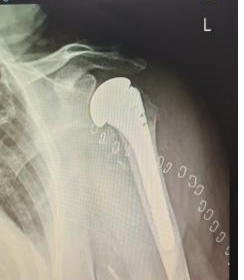

为确保手术成功,占卫兵主任团队于术前进行了周密规划:通过三维影像学重建明确骨骼结构细节,反复推演手术入路、假体选择及安装角度,制定个性化手术方案。手术中,团队在高清视野下精准分离组织,避开重要神经血管,顺利去除受损肱骨头,根据患者骨骼形态精准植入合适型号的人工假体,并调整至最佳位置,确保肩关节稳定性与活动度平衡。

▲患者术后